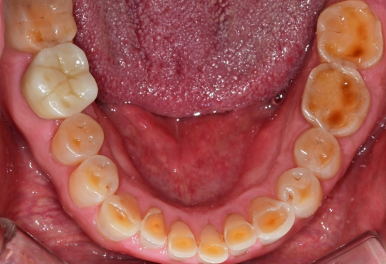

🦷 이갈이를 방치하면 생기는 문제

이갈이는 수면 중 무의식적으로

치아를 강하게 맞물리는 행동입니다.

문제는 그 힘이

👉 음식 씹는 힘보다 훨씬 강하다는 점입니다.

이로 인해 다음과 같은 문제가 생길 수 있습니다.

✔ 치아 마모 → 시림, 민감증 증가

✔ 치아 파절 → 금이 가거나 깨짐

✔ 보철물 손상 → 크라운, 임플란트 수명 단축

✔ 턱관절 장애 → 통증, 소리, 입 벌릴 때 불편함